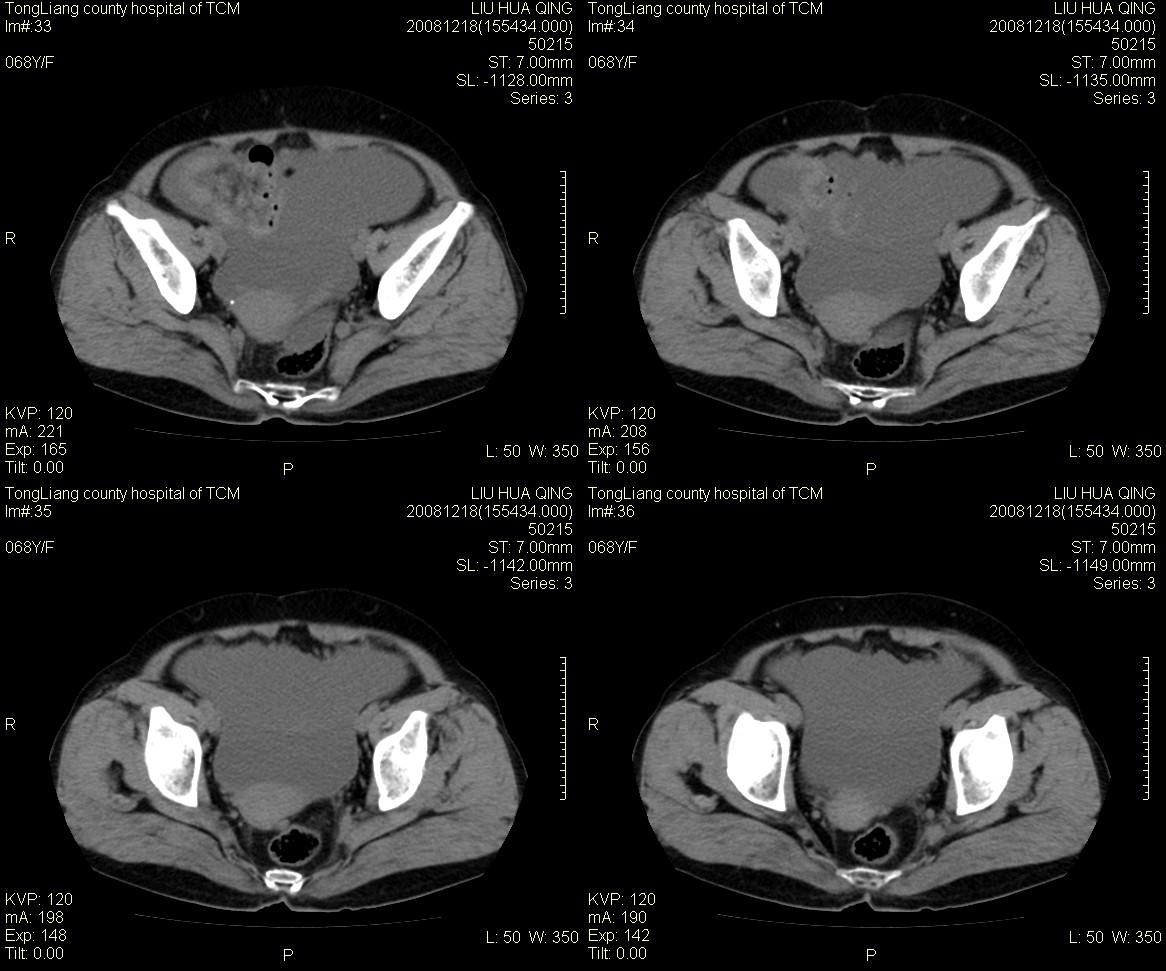

女,68y,下腹疼3月,一月半前院外ct示上腹未见异常。近1月来,症状加重。4天前入院,b超示胸腹水。今日呕吐频繁。  生化检查:  结核抗体阴性,血沉18mm/h, 癌胚抗原阴性,胸水细胞学检查见多数淋巴细胞。 白细胞总数5.4x10^12/l,血红蛋白104g/l.

腹腔积液可以肯定,原因?右侧下腹肠壁增厚,周围脂肪密度增高,粘连坏死?---梗阻坏死(不像)还是血栓坏死,占位?期待结果。

1)右侧腹腔前部见类似“网膜饼”样改变,考虑网膜转移瘤。2)腹水。

腹膜污染[大网膜增厚可见污垢征及小班结与饼片影,肠系膜增厚],大量腹水。考虑癌性腹膜炎,建议查腹水。结核待排.注意上腹部及胃肠道检查